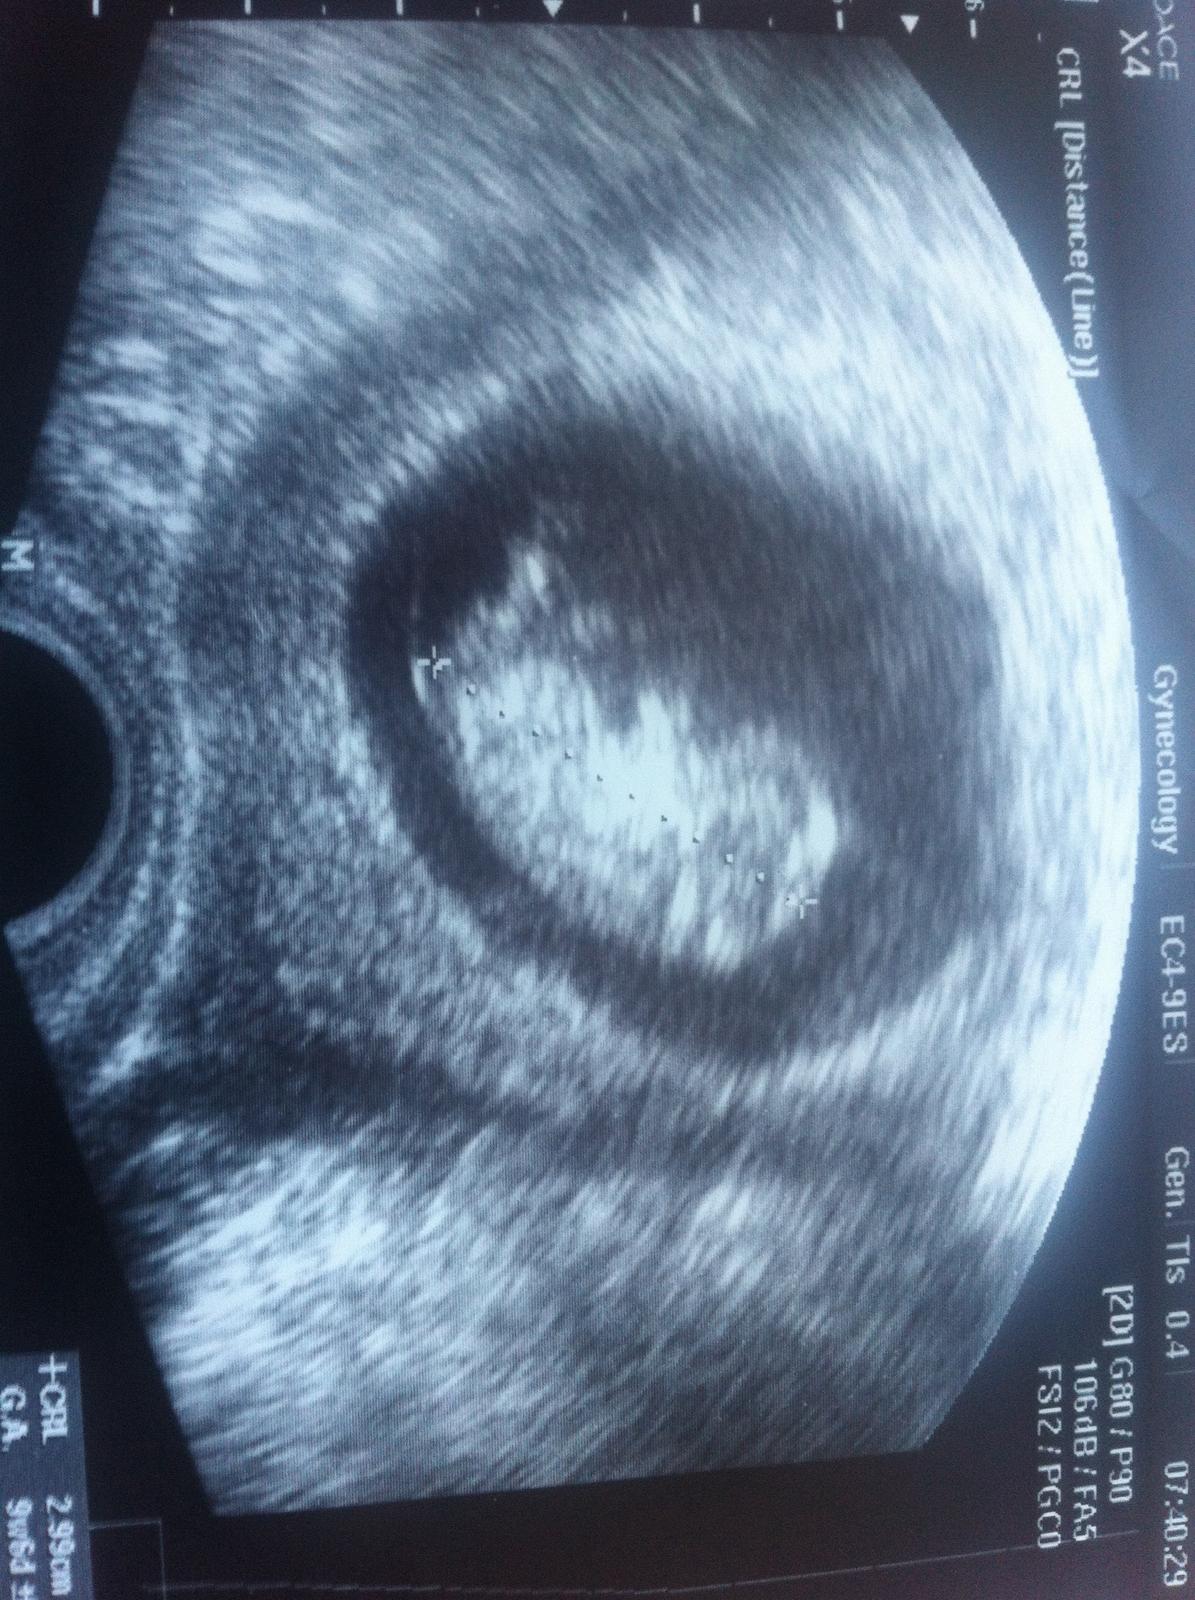

@delfi75 tady je naše "eskymo", říkala paní doktorka, že je to prý fakt krásný miminko🙂 nějak brzy🙂